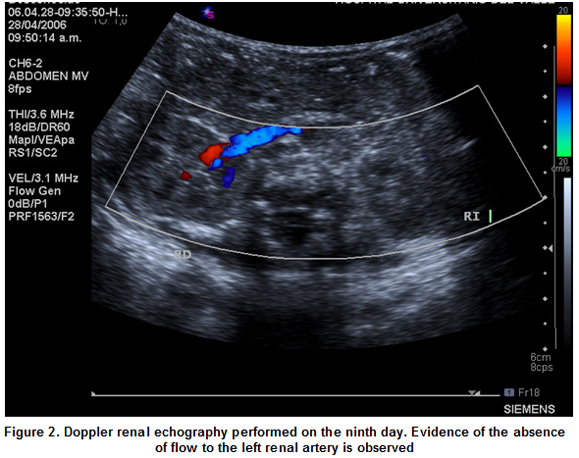

The case was present at the Neonatal Unit (CIRENA) of the Hospital Universitario del Valle. Corresponds to a masculine neonatal of 34 weeks, weighing 2,035 g, hospitalized for presenting signs of breathing difficulties, for which the umbilical venous and arterial catheterization was performed. On his fourth day of life, the patient presents high blood pressure and on the seventh day acrocyanosis is evidenced, absence of pulsations and arterial tension in the lower limbs is not present. on the eighth day the umbilical catheters are removed, the patient continues to be hyper tense and changes in his lower limbs, previously described are present. Echocardiography is performed observing a thromb at the aorta level. The diagnostic was confirmed on the ninth day by means of a doppler echocardiography (Figures 1, 2) which evidenced a thromb partially compromising the aorta and completely compromising the left renal artery by not detecting blood flow to the left kidney.